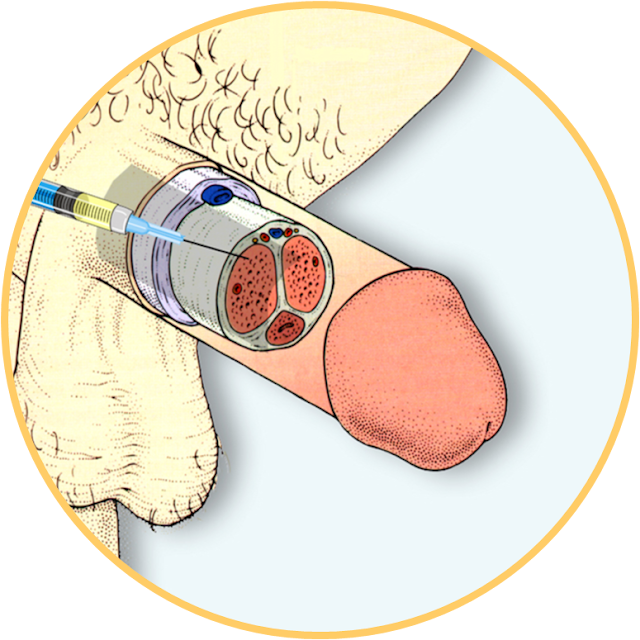

Os medicamentos aprovados especificamente para o seu tratamento são eficazes para muitos homens. Estes incluem medicamentos tomados por via oral (Viagra®, Cialis®, Levitra®), injetados directamente no pénis (Caverjet®; Prostaglandina E1), ou inseridos na uretra (MUSE ®- Medicated Urethral System for Erection; Alprostadil Transuretral).

Existem também Dispositivos de Vácuo e Tratamentos Cirúrgicos que podem ser úteis para homens com dificuldades eréteis.